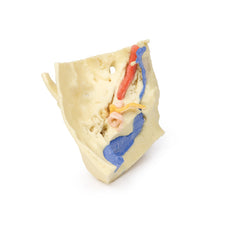

In the preserved midsagittal section there is preservation of the endocranial

contents, the nasal and oral cavities, and the pharynx to the level of the

laryngeal cartilages. The nasal cavity is preserved nearly intact, except for a

small window excised into the middle nasal concha to expose the ethmoid

air cells. A very large sphenoid sinus exists in the individual just superior

to the torus of the auditory tube in the nasopharynx. The oral cavity and

laryngopharynx are undissected, with the larynx only preserve just distal to the

level of the arytenoid cartilages and not including a clear set of vocal folds.